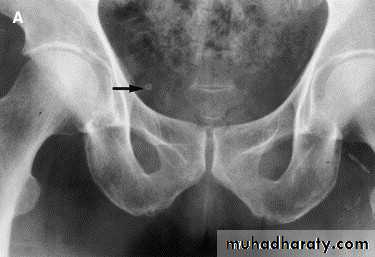

Vesicoureteric Reflux

Abnormal valve mechanism at UVJ resulting in reflux, ureteral dilatation, clubbed calices, eventual renal scaring.Clinical presentation: recurrent UTI, if long standing lead to renal scarring.

Two Types:

A. CONGENITAL REFLUX = PRIMARY REFLUX

Occurs in children, due to short submucosal ureteral tunnel, unilateral or bilateral.

Resolve spontaneiusly.

B. ACQUIRED REFLUX = SECONDARY REFLUX causes:

1. Duplication with ureterocele.2. Cystits.

3. Urethral obstruction.

4. VU reflux.

Diagnosis:

Mainly by voiding cystourethrography( VCUG) by urinary bladder catheterization and distension to confirm reflux.Also by US for assessment of renal parenchyma and scarring.

Primary VUR